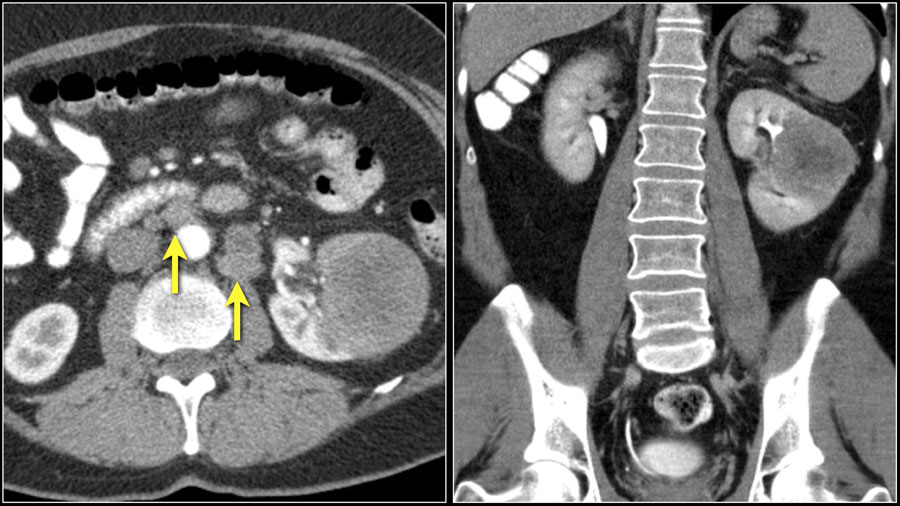

Направления для путешествий зависят в первую очередь от типа рака — рак легкого, например, дает метастазы в головной мозг, кости и надпочечники, а при раке почки образуются внутрисосудистые опухоли и опухоли костей. Раньше и обширнее метастазы наблюдаются у молодых людей, кроме того, метастазирование учащается с ростом опухоли. В среднем, как правило, метастазы появляются через 1-2 года после начала развития рака.

Когорта FUSCC